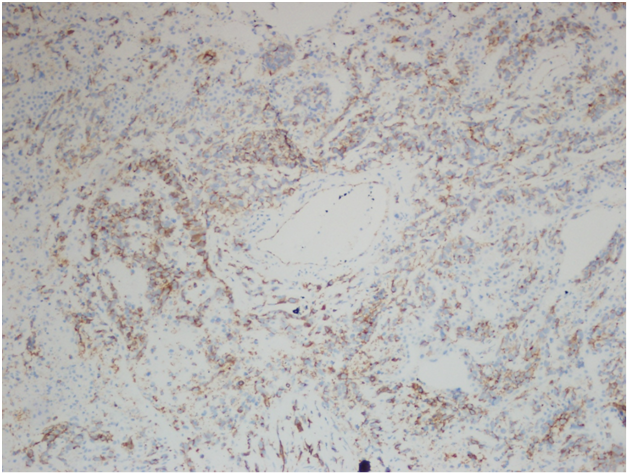

However, the wedge resection of the right lower lobe revealed angiosarcoma with lymphovascular invasion. This biopsy showed highly atypical and large malignant cells with increased mitoses (Figure 2A&2B). The immunohistochemical stains showed diffuse positivity for CD31, CD34, and vimentin (Figures 3A-3C). Stains for AE1/AE3 (Figure 3D), cam5.2, TTF-1, desmin, and OCT3/4 were negative. Along with the clinical history, a final diagnosis of angiosarcoma of the heart with metastases to the lungs was made.

Figure 3A Right lower lobe wedge resection. Immunohistochemical stain for CD31, 400x.